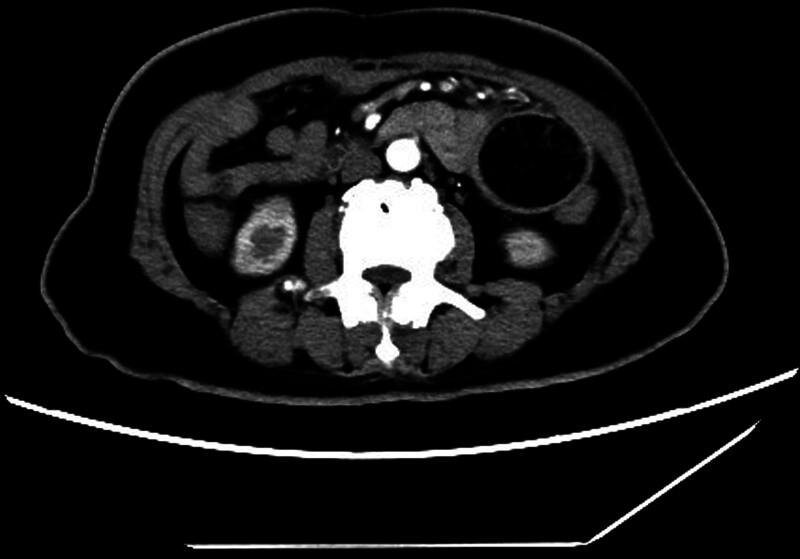

Fasting blood glucose was 21 mmol/L, urinary ketone body 3+, pondus hydrogenii (pH) 7.309, actual and standard bicarbonate decreased, and abdominal enhanced computed tomography showed a rounded low-density shadow with sharp edges and well-defined borders in the lumen of the bowel on the left side of the abdomen, with a size of 6 cm, and no significant enhancement within the lesion.

空腹血糖21 mmol/L,尿酮体3+,酸碱度(pH)7.309,实际碳酸氢盐和标准碳酸氢盐降低,腹部增强计算机断层扫描显示在腹部左侧肠腔内有一个边缘锐利、边界清晰的圆形低密度阴影,大小为6厘米,病变内部无明显强化。